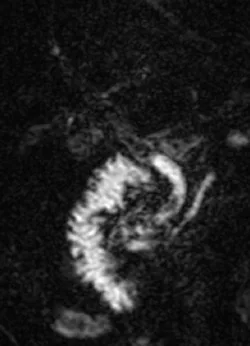

Figure 26.

A. Mise en évidence en bili-IRM de multiples dilatations anévrysmales des voies biliaires.

B. Les voies biliaires dilatées engainent le pédicule portal, visible sous la forme d’un point rehaussé au milieu des images kystiques (« dot sign », têtes de flèches). Cet aspect est caractéristique d’un Caroli. Il s’y associe ici une fibrose hépatique congénitale (des volumineuses varices spléniques d’hypertension portale sont visibles, flèche), ce qui fait porter le diagnostic de syndrome de Caroli